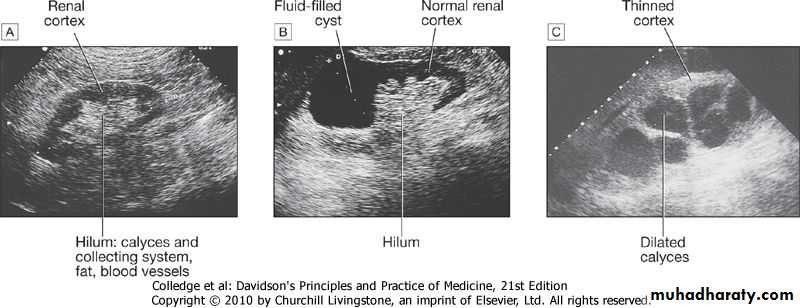

This quick, non-invasive technique is the first and often the only method required for renal imaging. It can show renal size and position, detect dilatation of the collecting system , distinguish tumours and cysts, and show other abdominal, pelvic and retroperitoneal pathology.Doppler techniques can show blood flow in extrarenal and larger intrarenal vessels. The resistivity index is the ratio of peak systolic and diastolic velocities, and is influenced by the resistance to flow through small intrarenal arteries. It may be elevated in various diseases, including acute glomerulonephritis and rejection of a renal transplant

In addition, it can image the prostate and bladder, and estimate completeness of emptying in suspected bladder outflow obstruction. In CKD ultrasonographic density of the renal cortex is increased and corticomedullary differentiation is lost. However, renal ultrasound is operator-dependent, and it is often less clear in obese patients.